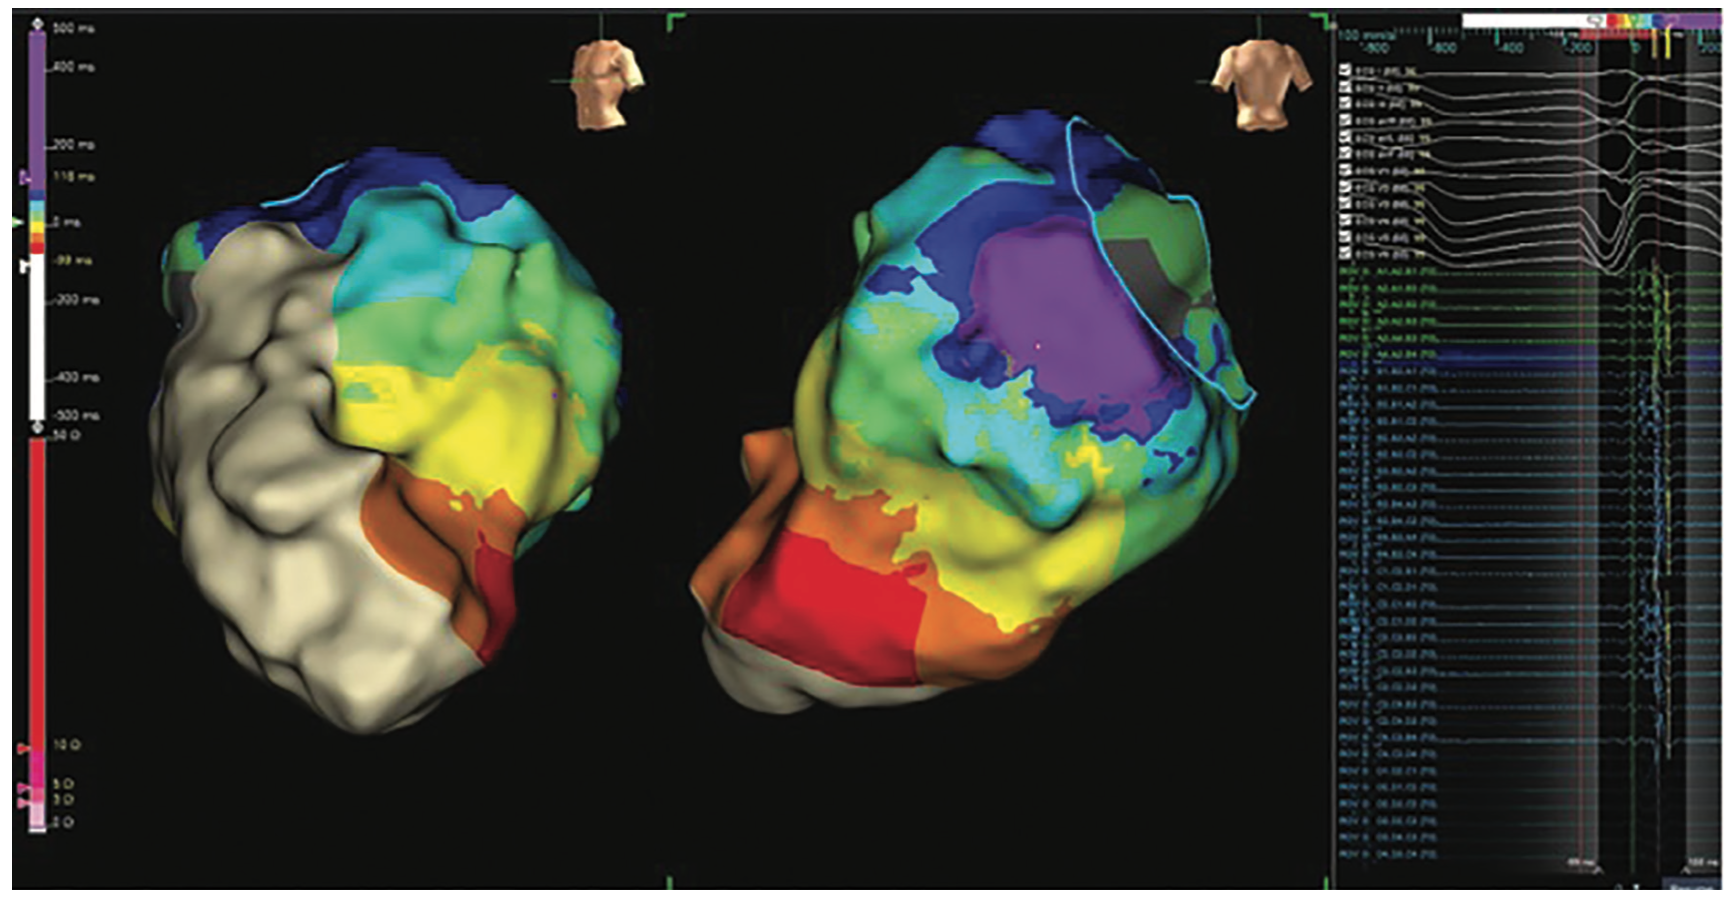

Conscious sedation was administered by the anesthesia team to lower the risk of hemodynamic compromise, which can be seen with general anesthesia. Because preop imaging suggested an epicardial substrate for VT, the patient’s chest was prepped in a sterile manner to facilitate possible epicardial access. An intracardiac echocardiography (ICE) catheter was inserted in the right atrium and ventricle. Ultrasound imaging of the LV showed basal inferolateral wall thinning with enhanced echogenicity of the epicardium, suggesting possible scar. Subsequent mapping of the LV was performed using a multipolar mapping catheter through a steerable sheath after a single transseptal puncture. A target activated clotting time (ACT) of 300-350 seconds was achieved with heparin boluses and a continuous infusion. To facilitate electroanatomic mapping, pacing was performed from the right ventricle using a quadripolar catheter. Using this approach, a detailed isochronal late activation and bipolar voltage map was created, confirming a predominantly basal inferolateral low voltage with areas of isochronal crowding (Figure 3). The patient was pretreated with intravenous (IV) norepinephrine (.03 mcg/kg/min) infusion in case of hypotension and programmed ventricular stimulation was performed. This induced several different right bundle branch block (RBBB) morphology monomorphic VTs with cycle lengths varying from 280-330 milliseconds, with positive precordial concordance suggestive of a basal LV origin requiring external cardioversion. However, none of the induced VTs had matching ICD electrograms to the clinical VT. As such, the decision was made to proceed with a substrate-based approach targeting endocardial substrate corresponding with regions with isochronal crowding and late potentials within the bipolar scar. A half-normal saline irrigated ablation catheter was introduced and ablation was performed (30-40 watts, duration of 60-300 seconds) with contact force >10g in the low-voltage basal LV segments (Figure 4).

The isochronal late activation map was repeated in the epicardium, identifying isochronal crowding in the basal inferolateral LV epicardium corresponding to the endocardial site (Figure 5). Coronary angiography confirmed a distance (>5 mm) of the left circumflex artery and its branches from the region of interest (Figure 6), and the phrenic nerve position was confirmed with high-output pacing and marked on the electroanatomic map. Extensive substrate-based ablation of the region of interest followed while avoiding the phrenic nerve. Irrigation of the catheter during epicardial ablation was lowered to 5 mL/min and the steerable sheath was aspirated regularly to maintain a dry pericardial space. After this, programmed stimulation was repeated and 2 more RBBB-morphology monomorphic VTs were induced. Pace mapping identified a more anterolateral epicardial origin and further ablation was performed in this area (Figure 7). The procedure was then concluded, the pericardium aspirated dry, and the epicardial sheath was replaced with a pigtail drain to be left in site overnight. ICE revealed no residual epicardial effusion, and 20 mL of 1% bupivacaine and 200 mg of triamcinolone were injected in the pericardial space for postprocedural analgesia and anti-inflammatory effect. All venous sheaths were removed and hemostasis was achieved using a closure device. IV heparin was continued for systemic anticoagulation given extensive endocardial LV ablation. There was no further drainage from the pericardial drain, which was pulled shortly thereafter, and colchicine was given for 2 weeks postablation.